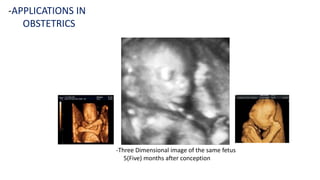

-APPLICATIONS IN OBSTETRICS

-Two Dimensional B Mode Ultrasound image of a fetus

-Three Dimensional image of the same fetus

5(Five) months after conception